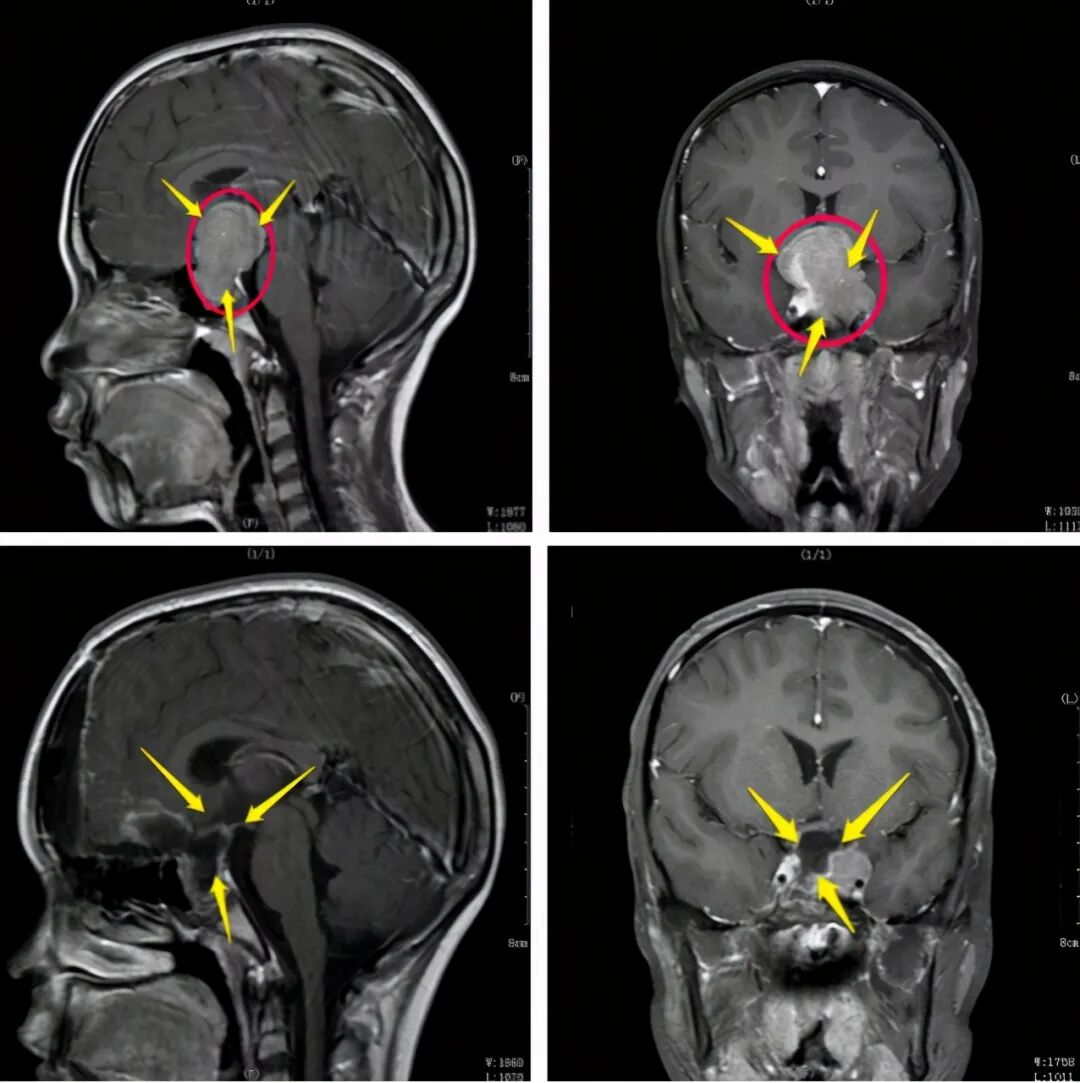

13 岁女孩,双眼视力持续性下降,一直以为是近视,直至出现头疼,就诊确诊为 6x5x5cm 脑膜瘤。

昆明三博脑科医院院长张永力介绍:「 这三个案例病人年龄不一样,患的肿瘤不一样,但都有一个共同点,就是延误了早期诊断,觉得眼睛的问题与脑肿瘤扯不上关系,长期去看耳鼻喉科和眼科,等症状加重时才发现是脑部的问题,发现时脑瘤已经长得很大,不但让治疗、后期维养恢复变得更加困难,同时也增加了治疗费用,甚至的有的患者虽然摘除了肿瘤,但视力恢复到正常的机会已大为降低, 给家人及患者都带来巨大的困扰。」